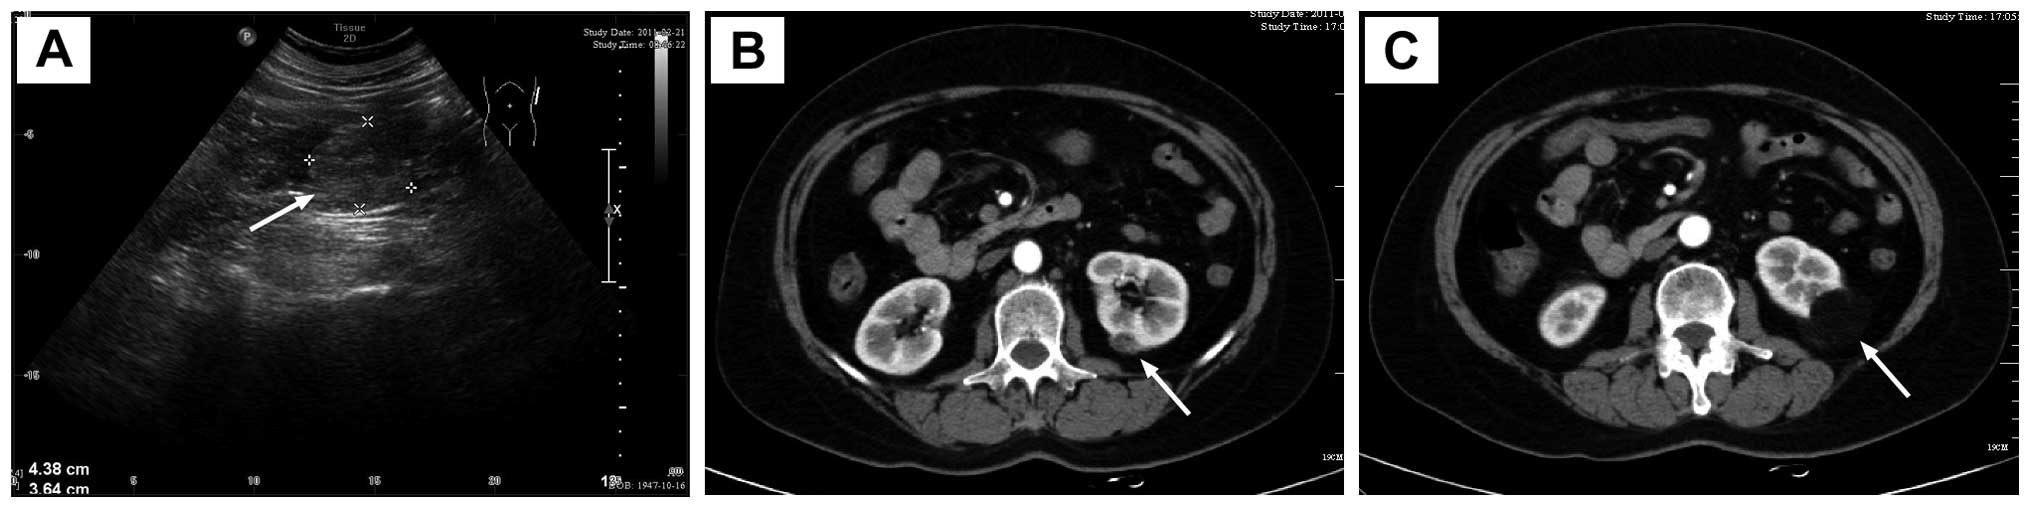

However, the patient was re-admitted on the 14th postoperative day due to the discharge of increasingly milky, thin, odourless fluid every day from the unclosed external orifice of the drainage tube. The amount of fluid reached 800 ml on the second day after re-admission. The creatinine concentrations of the fluid and urine were 1847 and 4640 μmol/l, respectively. The result of qualitative analysis of chyle was negative. CT urography (Fig. 2A–E) revealed a clear renal collecting system and no significant hydronephrosis. However, contrast remained in the left kidney and upper ureter and leakage in the perirenal space and along the psoas muscle, and was drained out of the body through the drainage tube. Moreover, no contrast agent was observed in the middle and lower ureter. In MR urography images (Fig. 2F), there was fluid signal in the perirenal space, particularly inside and below the left kidney. The results of CT and MR urography revealed left urinary fistula. A 5-F ureteral catheter was inserted into the left ureter for retrograde pyelography and elevated ∼20 cm but did not pass to the left renal pelvis. Then reoperation was performed on the 16th postoperative day to explore the left kidney and ureter in order to relieve the obstruction, allow unobstructed drainage and save renal function (Fig. 3). During the reoperation, almost complete occlusion of ureteral stricture was found in the upper ureter 5 cm from the left ureteropelvic junction. The ureter near the stricture was enfolded by fibrin glue and exhibited marked stiffness and adhesion. The lesion of the ureter was resected and the ureter was anastomosed end to end with the routine double-J stent (Fig. 4). Pathological examination of surgical specimens revealed fat fibrous scar tissue hyperplasia with inflammatory cell infiltration. The double-J tube was removed by cystoscopy two months after the second surgery. The patient recovered completely without exudate.

Figure 2

Postoperative imaging showing urinary fistula. (A–E) Urinary fistula (arrow) was detected by CT urography. (F) Urinary fistula (arrow) was detected by MR urography.